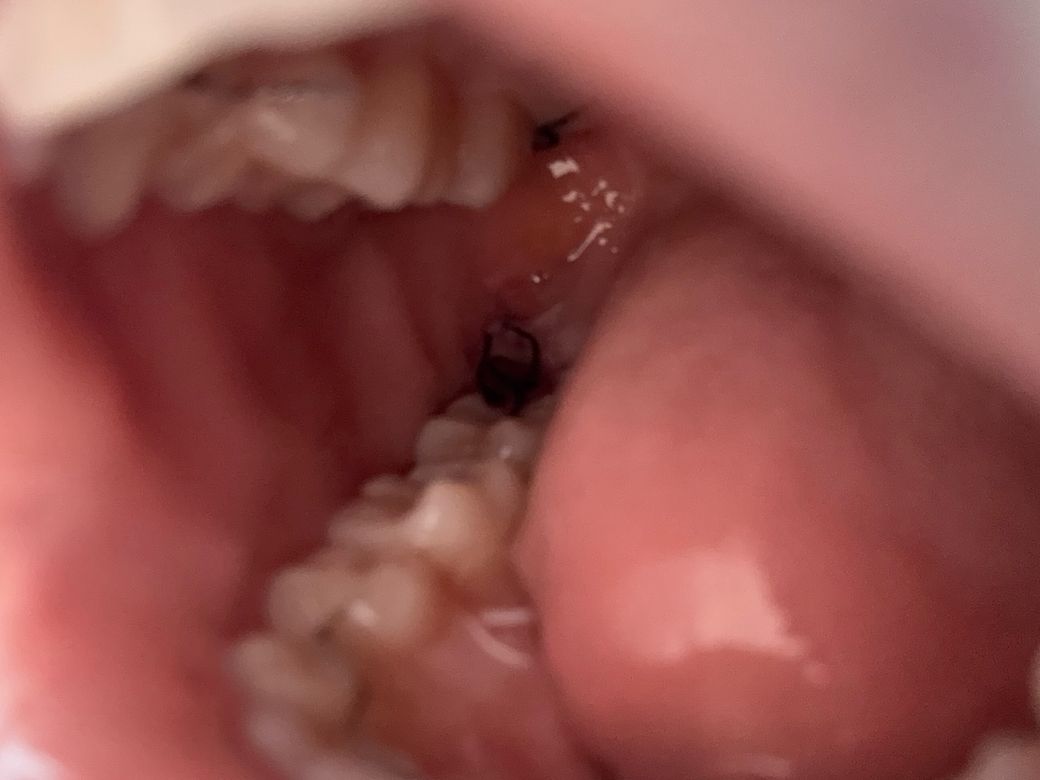

사랑니 발치 4일차입니다ㅠㅠ 확인 부탁드립니다

통증은 타이레놀+처방약 먹으면 잡히긴 하지만 아직 볼에 붓기는 남아 있습니다 ㅠㅠ… 다른 분들 사진 보니 보통 4일차에는 살이 조금씩 차는 것 같던데 저는 피떡이 져있어 염증일까 여쭤보고 싶습니다… 잘 회복 중인 거 맞을까요??

• 1번 째 사진

특별히 문제가 보이지는 않습니다. 살이 회복되는 것은 보통 수개월 정도는 소요되는 편입니다.

사진상으로 잘 회복되고 잇는거 같습니다. 사랑니 발치를 하고나서 잇몸이 아무는데는 최소 한달정도 시간이 소요됩니다.

사진상 크게 치유에 문제가 있어보이진 않습니다.